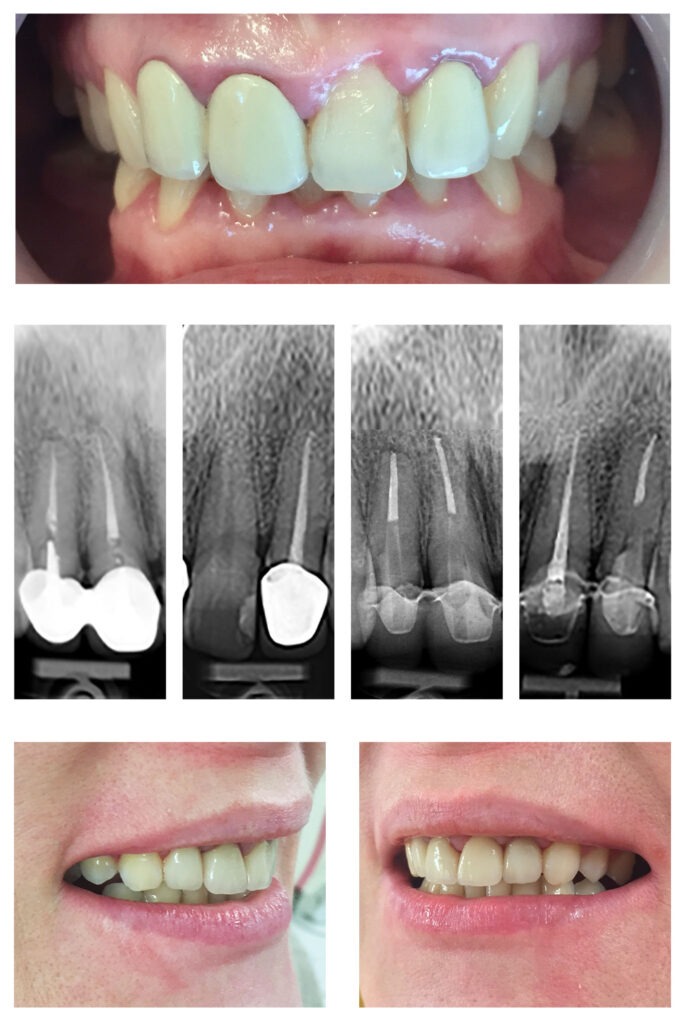

Extruzia ortodontică a dinților cu distrucție subgingivală accentuată salvează unii dinți de la extracție…pentru că dintele natural este cel mai bun implant. Săgețile evidențiază cât de multă extruzie am reușit să obținem în câteva luni.